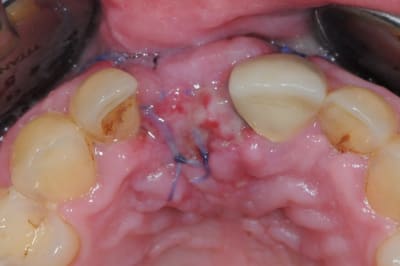

> Ci joint cas avec biobank, très bonne stabilité et consistance a la réouverture

> a 9 mois.

pourquoi utilises tu encore cette merde de vicryl, tu gagnerais beaucoup à passer au PTFE.

Dommage que tu n'aies pas décalé tes incisions de décharges, ça t'aurait évité d'avoir une récession gingivale post operatoire sur 21 !

oui, très juste, c'était une grooossssse connerie de ma part. je sais pas ce qui m'a pris, je comprends pas!

j'ai retrouvé, mais c'est le correspondant qui à posé l'implant et les photos sont pas top :(

ceux sont les photos du correspondant .